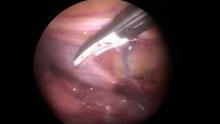

- Following pulmonary vein (PV) isolation, three left VATS ports (5 mm port in the second intercostal space (ICS), 5 mm port in the midaxillary line at fourth ICS, and 12 mm port in the sixth ICS in the posterior axillary) line were performed.

- A double-lumen endotracheal tube was placed prior to the beginning of the case. The left lung was deflated, and the pericardium was opened parallel and below the phrenic nerve.

- The LA appendage was envisioned and measured, and a 35 mm pro-2 AtriClip device was deployed through the lower 12 mm port around the base of the LA appendage.